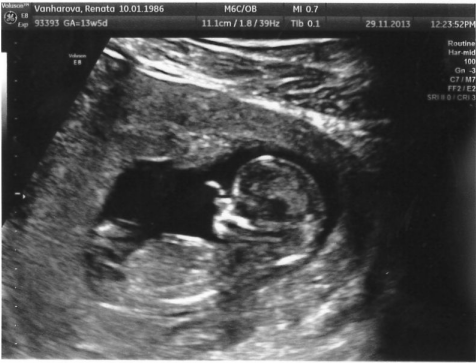

(12+5) tak jsem po screeningu - Apolinář v Praze, nic jsem neplatila (jen za fotečku)

vyšetření trvalo asi 20 minut a klidně bych tam ležela dál a dívala se na toho prďouska do nekonečna, sice jsem dala na rady a vypila studenou vodu než jsem tam šla, ale mimčo i tak spinkalo, trochu jsme do něj šťouchali tak se jen malinko otočil a spinkal spokojeně dál a ještě k tomu s ručičkou přes tlamičku abychom se na něj nedívali

vše v pořádku, tak jsme konečně klidnější, další UZ na konci ledna, a pohlaví zatím nevím